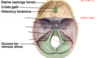

What are the names of these holes and which cranial nerves come out of each.

What do each of these do also?